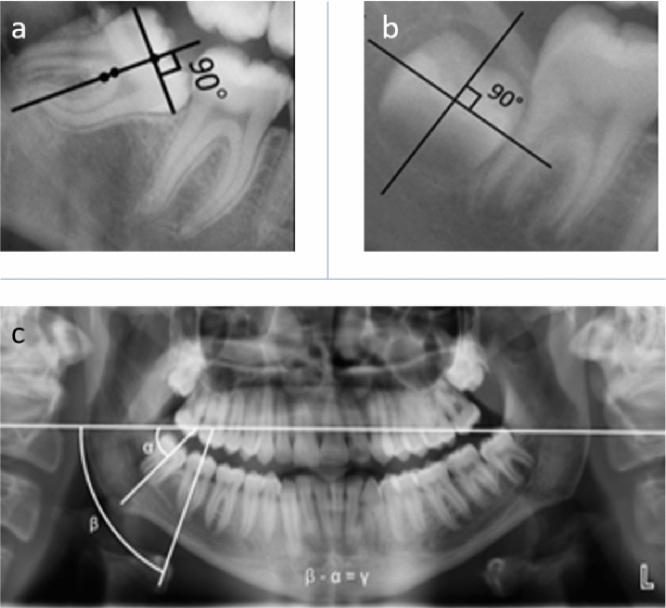

Prediction of lower third molar eruption is crucial for its timely extraction. Therefore, the primary aim of this study was to investigate the prediction of lower third molar eruption and its uprighting with the assistance of an artificial intelligence (AI) tool. The secondary aim was identifying the incidence of fully erupted lower third molars with hygienic cleansability. In total, 771 patients having two panoramic radiographs were recruited, where the first radiograph was acquired at 8-15 years of age (T1) and the second acquisition was between 16 and 23 years (T2). The predictive model for third molar eruption could not be obtained as few teeth reached full eruption. However, uprighting model at T2 showed that in cases with sufficient retromolar space, an initial angulation of < 32° predicted uprighting. Full eruption was observed for 13.9% of the teeth, and only 1.7% showed hygienic cleansability. The predictions model of third molar uprighting could act as a valuable aid for guiding a clinician with the decision-making process of extracting third molars which fail to erupt in an upright fashion. In addition, a low incidence of fully erupted molars with hygienic cleansability suggest that a clinician might opt for prophylactic extraction.

预测下颌第三磨牙的萌出对于及时拔除至关重要。因此,本研究的主要目的是利用人工智能(AI)工具探讨下颌第三磨牙萌出及其直立的预测。次要目的是确定具有卫生清洁性的完全萌出下颌第三磨牙的发生率。共招募了 771 名接受了两次全景片检查的患者,第一次拍摄在 8-15 岁(T1),第二次拍摄在 16-23 岁(T2)。由于很少有牙齿完全萌出,因此无法获得第三磨牙萌出的预测模型。然而,T2 时的直立模型表明,在具有足够远中间隙的情况下,初始角度<32°可预测直立。13.9%的牙齿完全萌出,只有 1.7%具有卫生清洁性。第三磨牙直立预测模型可以作为指导临床医生进行决策的有价值的辅助工具,以决定那些未以直立方式萌出的第三磨牙是否需要拔除。此外,具有卫生清洁性的完全萌出磨牙发生率较低,提示临床医生可能会选择预防性拔除。